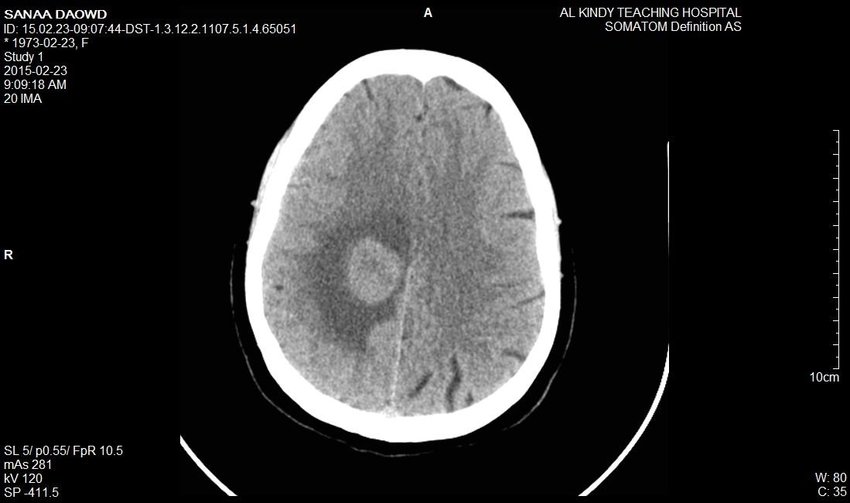

Tomografię komputerową stosuje się najczęściej przy urazach oraz podejrzeniach nowotworów, udarów, krwiaków, ropni, padaczki, czy choroby Alzheimera. A oto przykłady:

Skan CT nowotworu mózgu